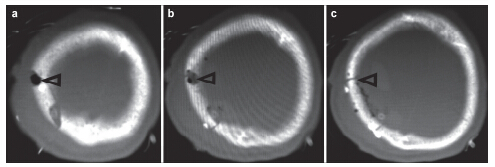

摘要 Objectives: In this case report, we describe the design, fabrication and clinical outcomes of a novel bioresorbable, mineralized collagen burr-hole plug for the reconstruction of craniotomy burr-holes.

Methods: Mineralized collagen burr-hole plugs were fabricated via a biomimetic mineralization process. The biomimetic mineralized collagen has a similar chemical composition and microstructure to natural bone tissue, thereby possessing good biocompatibility and osteoconductivity. The mineralized collagen burr-hole plugs were implanted into three patients, and clinical outcomes were evaluated at one-year follow-ups.

Results: All bone defects healed very well using the mineralized collagen burr-hole plugs, and there were no adverse reactions at the surgical sites.

Conclusions: The clinical outcomes indicated that the mineralized collagen was effective for reconstructing burr-holes in the skull after craniotomy.

Abstract: Objectives: In this case report, we describe the design, fabrication and clinical outcomes of a novel bioresorbable, mineralized collagen burr-hole plug for the reconstruction of craniotomy burr-holes.